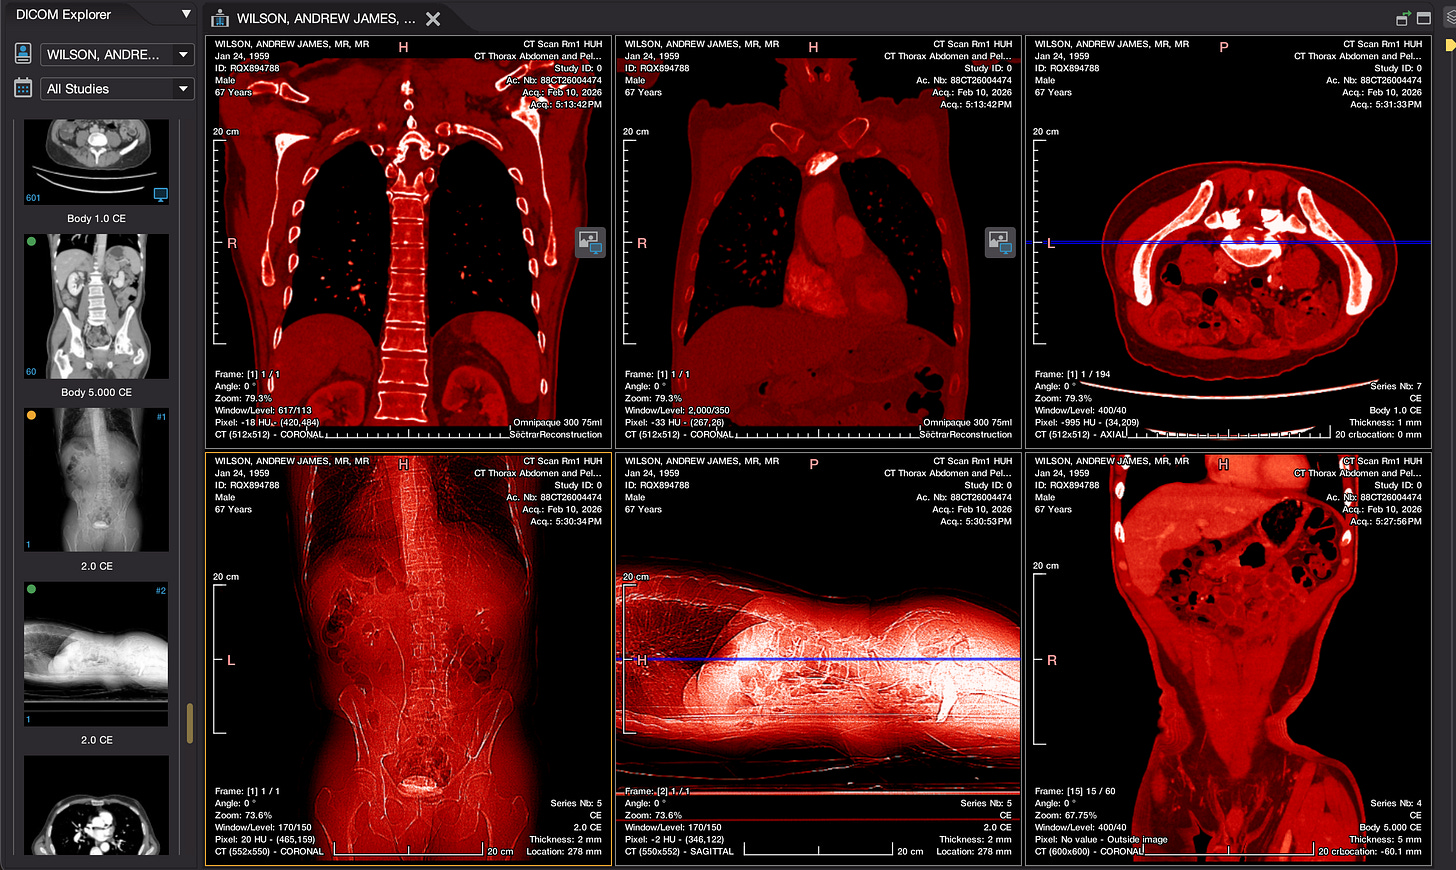

A PET scan is organised a few days later, at St Barts Hospital, in the shadow of St Paul’s. The body is flooded with a tracer radioactive fluid, after which you are locked into a lead-lined box for three-quarters of an hour to allow it to bake in. The scanner then detects where the tracer has been absorbed by cell growth anywhere in the body it is directed, producing reams of flowing light captured to film, copies of which—scans of my own body—are used throughout this post.

The moment I saw the very first scan the doctors showed me (bottom right, above: an MRI, rather than PET, as it happens)—on a small monitor wheeled into my cubicle at the Homerton—seemed to say everything at once. As I turned my head to look at the image of my brain on the monitor, I glimpsed also the tattoo on my left arm suddenly aligned with it (bottom left)—a tattoo of a bhikkhu meditating in flames, inked twenty years earlier, with the bhikkhu meditating as descibed in the Buddha’s Adittapariyaya Sutta (Fire Sermon)—such that the tattoo of the bhikkhu and the scan of the brain, aligned properly. One presaged the other by years, holding out its hand to the other. They reflected each other so neatly, with the tumour in the cerebellum showing up as the red-orange fire bursting through from within, which the bhikkhu sits through.

On seeing further scans, I recognised, eg., my rib cage as something indeed very much like the frame of Israel’s tents (above, top left), beaming on the shore of the infinite (Blake), but also, in the twisting images of the torso, I am struck by the sprawling energies at play, unleashed by disease. No longer is there the assumed underlying durable person, sealed away from the totality, cybernetically establishing their personal border by fending off and repurposing the chaos, sickness and disorder without. Instead, raw energies start to coalesce, turning Urizenic, mechanical rigidity into flashes, streaks and pulses of contending light.